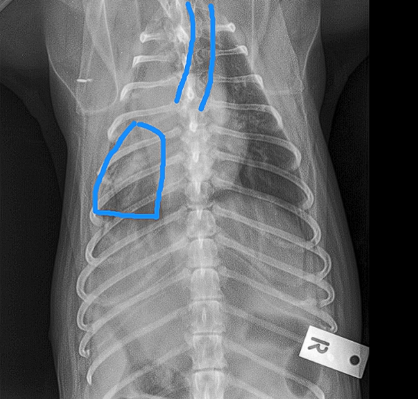

Little area of consolidation but nothing else significant

DX - chronic cough suspicions for airaway disease due to chronic unproductive cough

On left hand side (actually right ariway) airway is compressed

Wouldn’t be ablse to see mass on radiograph as heart borders block ti

Bronchoscopy - wouldn’t be able to see the mass - only see the collapse but not what caused it

CT is our bitch